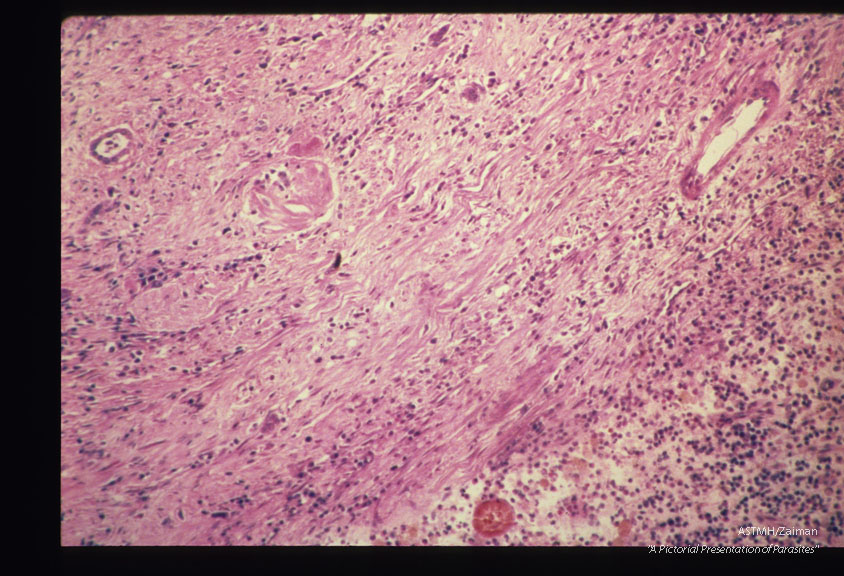

Leisegang rings have been mistaken for eggs of the giant kidney worm Dioctophvma renale by multiple authors. They are periodic precipitation zones formed from supersaturated solutions in colloidal systems. These slides are from one such case.

Leisegang rings

Description: Leisegang rings have been mistaken for eggs of the giant kidney worm Dioctophvma renale by multiple authors. They are periodic precipitation zones formed from supersaturated solutions in colloidal systems. These slides are from one such case.